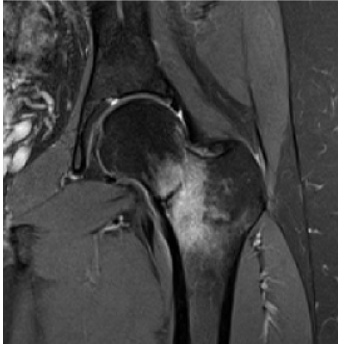

Femoral Neck Fractures

Femoral neck fractures are commonly seen in elderly patients after low‑energy falls, as well as in younger patients following high‑energy trauma such as motor vehicle accidents. While many are readily apparent on hip or pelvis radiographs, femoral neck stress fractures can be more elusive. These injuries occur from repetitive loading, often in runners or military personnel. If missed, continued weightbearing can lead to fracture displacement or femoral head avascular necrosis. In patients with persistent groin or thigh pain and negative radiographs, MRI is indicated. Early diagnosis allows for protected weightbearing and prevents progression to catastrophic injury.